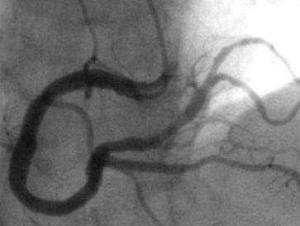

心臟造影有冠狀動脈造影和心臟(心房、心室)造影。冠脈造影就是用一根細如髮絲的導管沿著橈動脈(手腕處)或股動脈(大腿處)的人為入口延行到心臟的冠狀動脈開口處,然後把造影劑(在X光下顯影)注入冠狀動脈,這樣冠狀動脈內部的形態就可以顯示出來,例如看冠脈有沒有狹窄、斑塊等,但基本上不能通過這個檢查來了解心臟形態的,主要還是了解冠脈的內部形態及冠脈內的血流速度。

※心臟造影是一種檢查手段。醫生懷疑病人是否有冠心病,檢查結果比較準確,因此稱此項診斷為“金診斷”,如果查出有冠狀動脈血管狹窄或者堵塞等可以作進一步的治療如放置支架等。造影不能治療高血壓、也不能治療早搏。